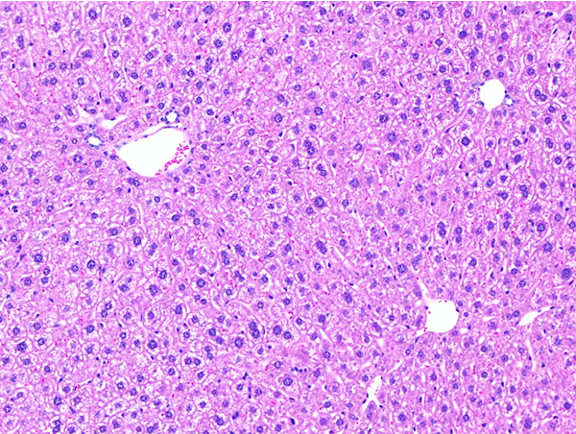

Figure 6: Histopathology for C57BL/6NTac mice placed on D09100310 diet (MASH B6NTac) or kept on chow diet (Control B6NTac) from 6 weeks of age. Animals were on diet for 27, 35 or 53 weeks. Hematoxylin and eosin (H&E) staining illustrates morphological changes including steatosis and infiltration of immune cells. Activated HSCs were identified in liver sections by using a rabbit polyclonal antibody to alpha-smooth muscle actin (a-SMA) (1:500 dilution; ab5694; Abcam, Cambridge, MA) which was detected by an anti-rabbit IgG embedded polymer with embedded horseradish peroxidase and visualized with 3,3′-diaminobenzidine (DAB) chromogen (Agilent, Carpentaria, CA). Hepatocellular lipid droplets were identified by visualization of the lipid-binding protein adipophilin known to be expressed in steatotic livers. Sections of livers were probed using a rabbit polyclonal anti-adipophilin antibody (1:200 dilution; NB110-40877, Novus Biologics, Littleton, CO) which was detected by an anti-rabbit IgG embedded polymer with embedded horseradish peroxidase and visualized with 3,3′-diaminobenzidine (DAB) chromogen (Aligent, Carpentaria, CA). Picrosirius red (PSR) staining illustrates collagen I and III fibers and is used to measure fibrosis. The same individual MASH or control animal is shown for all four stains in a particular time point. Different individual animals were used for each time point (i.e. data is not longitudinal by animal). Histopathology services provided by IDEXX BioAnalytics.